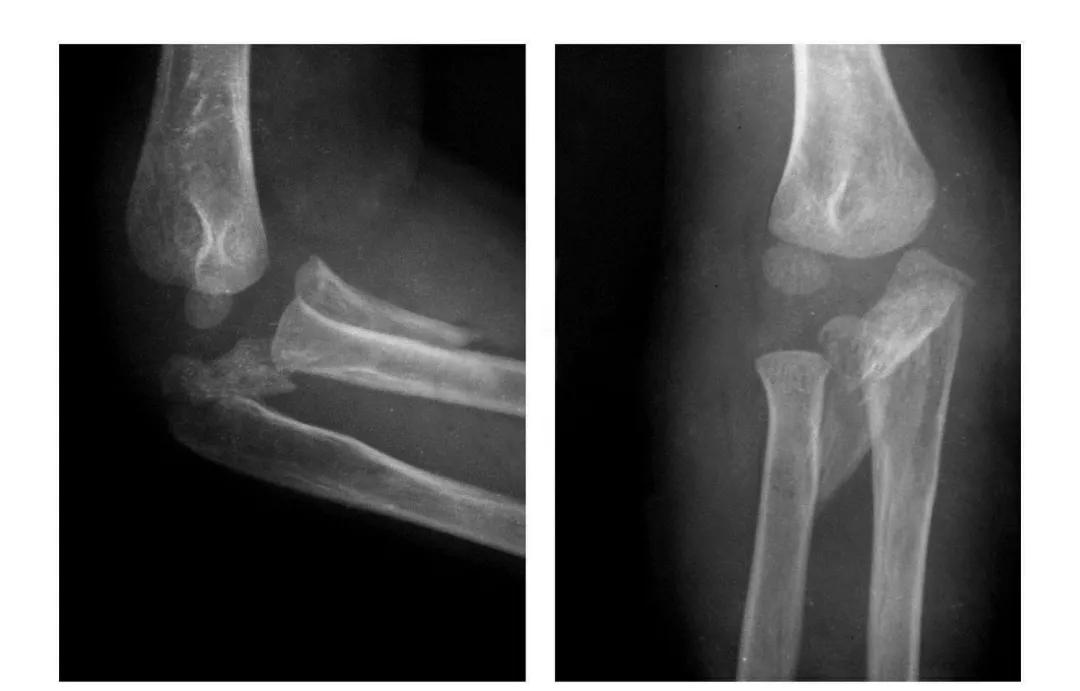

肱骨小头冠状面骨折

(一)完全骨折

本病亦称哈-斯(Hahn-Steinthal)型骨折

例1:肱骨小头基底部呈冠状面骨折,骨折块呈半球状向肘前上方移位。

例2:肱骨小头基底部冠状面骨折,骨折块呈半球状向肘前移位并肱骨内上髁无移位骨折。